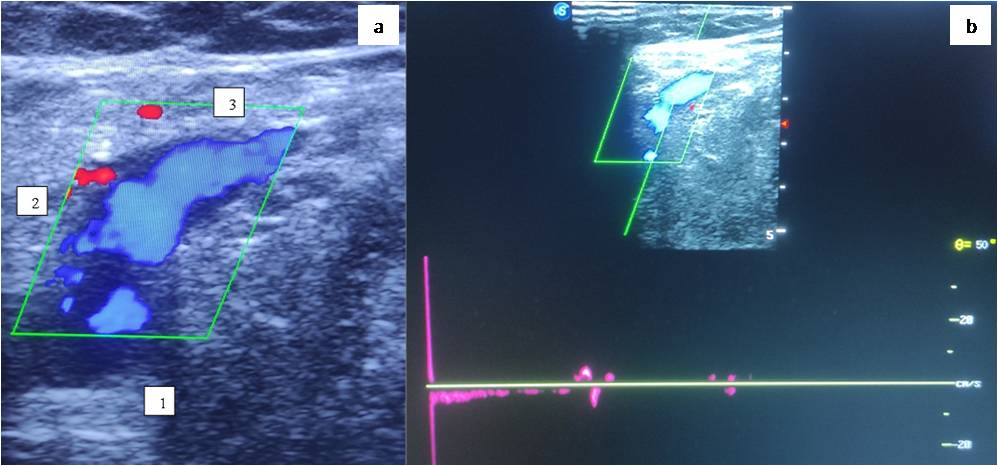

On a follow-up examination two years later: the patient notes a good cosmetic result of surgery. On DS, the GSV is patent, competent (Figure 4).

Fig. 4. Female patient Z., 35 years old. Control ultrasound scan of the vessels of saphenofemoral junction region in two years after the surgical intervention: a — color Doppler imaging mode; b — spectral Doppler mode.

Notes: 1 — common femoral vein, 2 — saphenofemoral junction, 3 — great saphenous vein.

DS of the lower limb veins: deep veins patent, full compression, moderate insufficiency of the valves of the common femoral vein, of the deep femoral vein; other segments of deep veins competent. GSV, SSV patent, competent. An incompetent PV along the left thigh posterolateral surface, associated with the deep femoral vein.